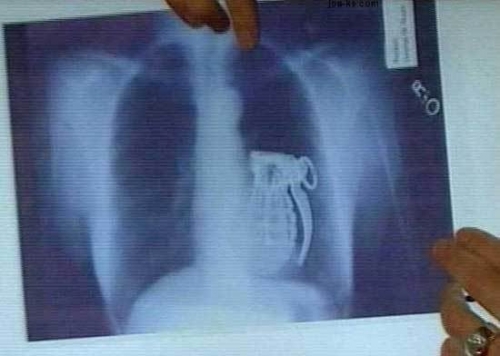

Смешные картинки и мемы ко Дню рентгенолога